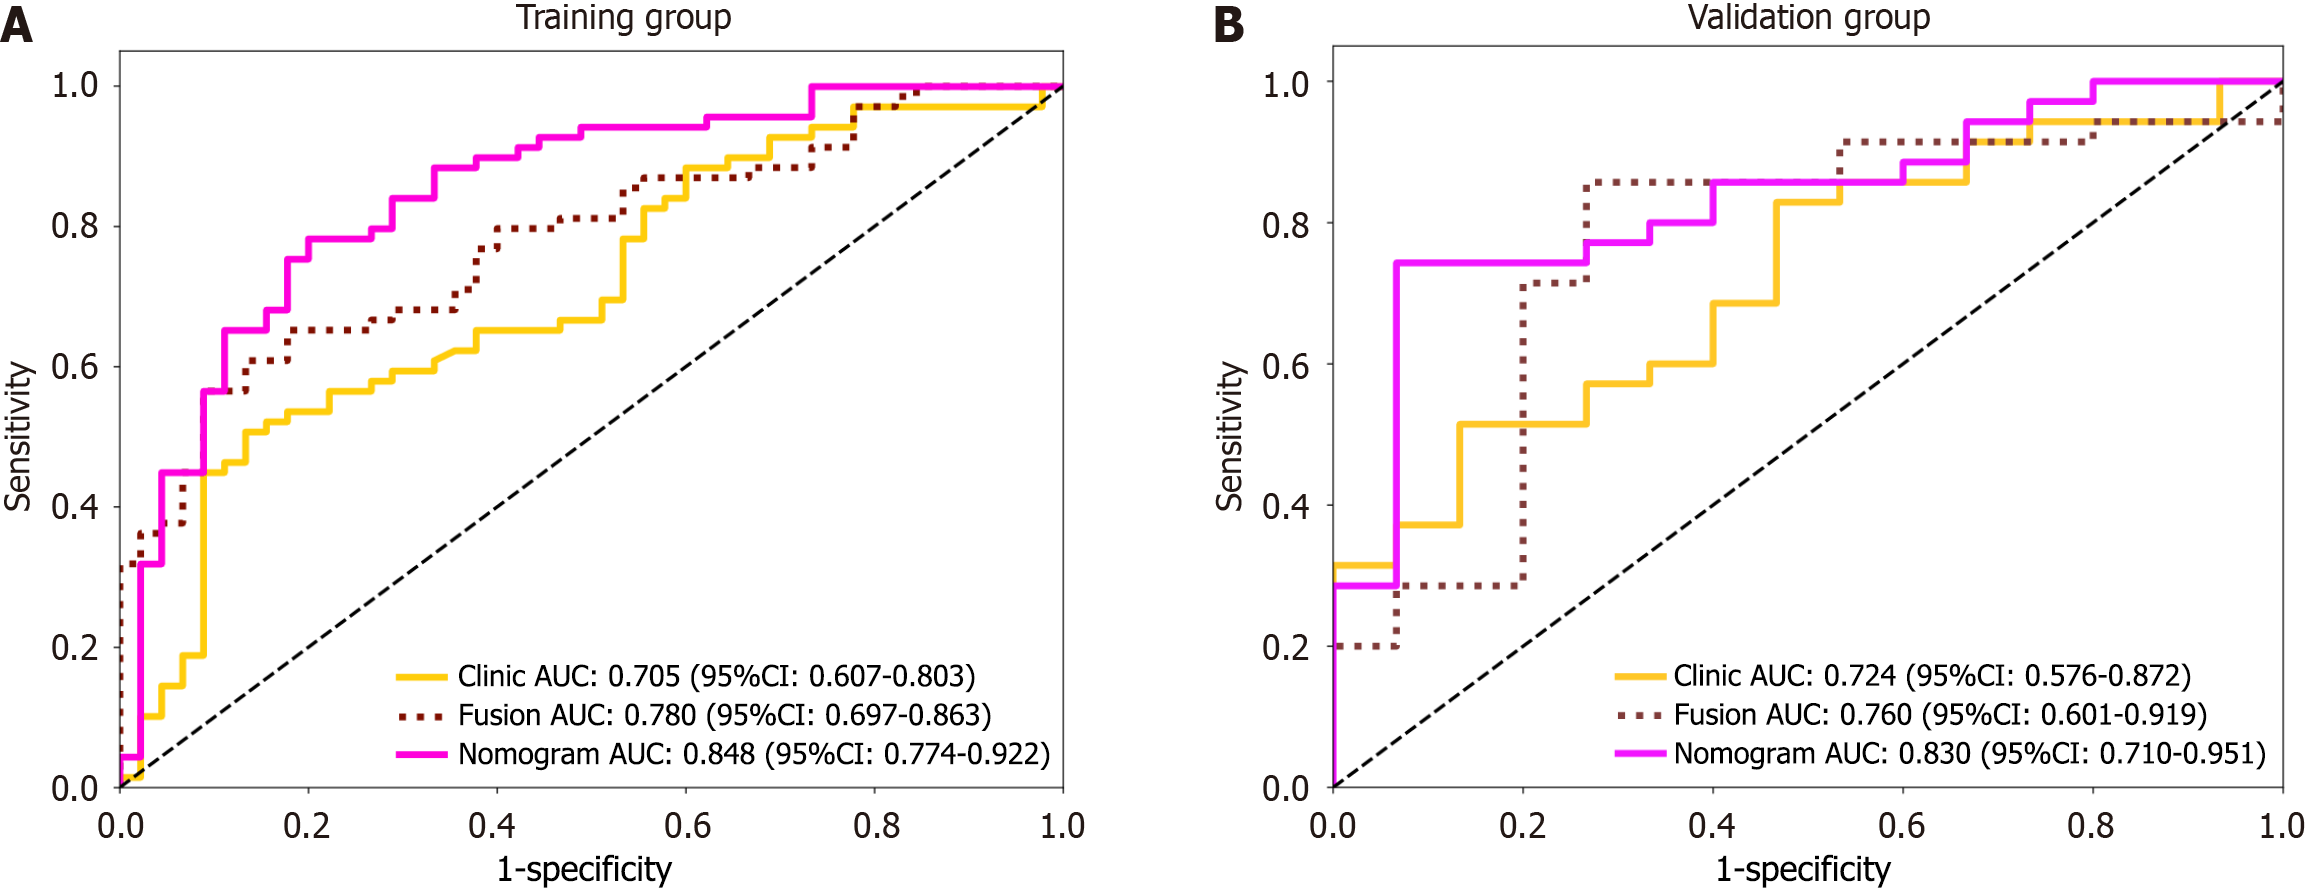

In total, 164 HCC patients, namely, 104 patients with high Ki-67 expression and 60 with low Ki-67 expression, were included. Compared with the models in which only intratumoral or peritumoral features were used, the fusion model in which intratumoral and peritumoral features were combined demonstrated stronger predictive ability. Moreover, the clinical-radiomics model including the Radscore and clinical features had higher predictive performance than did the fusion model (area under the ROC curve = 0.848 vs 0.780 in the training group, area under the ROC curve = 0.830 vs 0.760 in the validation group). The calibration curve showed good consistency between the predicted probability and the actual probability, and the decision curve further confirmed its clinical benefit.

Using the logistic regression algorithm, we constructed predictive models and selected the best-performing model. Among the three models in the validation group, the fusion model had the highest predictive capability, with an AUC of 0.760 (0.601-0.919), which surpassed those of the intratumoral model [AUC of 0.703 (0.526-0.880)] and the peritumoral model [AUC of 0.716 (0.541-0.892)], as shown in Figure 4. The ROC curve for the training group is presented in Supplementary Figure 4. To further demonstrate the performance of the model, we plotted waterfall plots for each of the three prediction models. The results showed that the three models have high accuracy in assessing the expression level of Ki-67. The waterfall plot of the validation group is shown in Figure 5, and the waterfall plot of the training group is shown in Supplementary Figure 5.

A logistic regression model was developed that incorporated ALT, hepatitis B virus infection, and cirrhosis. The model demonstrated an AUC of 0.705 (0.607-0.803) in the training group and 0.724 (0.576-0.872) in the validation group, as illustrated in Supplementary Figure 6.

A combined clinical-radiomic nomogram was developed by integrating the Radscore from the fusion model with the clinical characteristics from the clinical model. This nomogram achieved an AUC of 0.848 (0.774-0.922) in the training group and 0.830 (0.710-0.951) in the validation group, demonstrating superior predictive performance compared with both the radiomic fusion model and the clinical model alone, as shown in Figures 6 and 7.